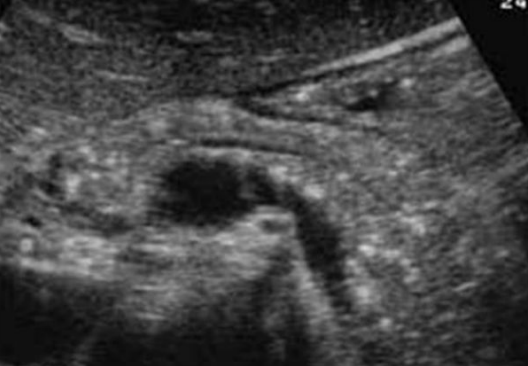

Describe this image

Diagnosis?

Transverse view of the pancreas

Pancreas appears to be swollen/enlarged with increased echogenicity and has peripancreatic fluid

Dx: acute pancreatitis